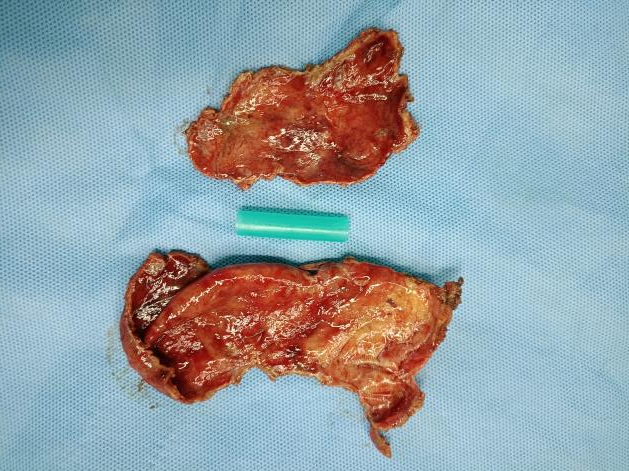

经泌尿外科团队讨论后,决定为患者施行腹腔镜下膀胱巨大憩室切除术,手术顺利。术后拔除尿管后,罗大叔排尿通畅、症状消失,非常满意。出院时罗大叔高兴的说:“我以为要开大刀,没想到几个小孔就解决了,你们的技术真的好!” 术前影像 术后影像 切下来的膀胱憩室 微创小孔 科普知识 什么是膀胱憩室?它有什么危害吗? 膀胱憩室主要是由于患者膀胱肌肉先天性的薄弱,或者是由于尿路梗阻导致的膀胱内压的升高,最终在膀胱壁表面形成了一个膀胱黏膜经膀胱壁肌层向外膨出的囊袋,就好像是多了一个膀胱一样。如果憩室较小,可无明显症状。但如果憩室较大,则会出现排尿困难、尿频、尿急、尿痛、血尿以及两段排尿等相关症状,严重时可出现严重的并发症。 并发症: 1.便秘-膀胱憩室压迫到了患者的直肠,从而导致患者出现便秘。 2.难产-巨大的膀胱憩室压迫到子宫,导致女性患者难产。 3.憩室感染、憩室结石-患者可出现尿频、尿急、尿痛等尿路感染的症状,严重者甚至并发憩室结石。 4.尿路梗阻-憩室增大可以压迫输尿管使之产生位移,从而出现梗阻。 5.肾功能不全或者肾衰竭-当患者的憩室增大导致出现尿路梗阻,如梗阻进一步发展,使得肾小囊内压力增高造成肾小球率过滤的降低,尿量减少,肌酐、尿素氮排出受阻,严重者可以出现肾功能不全或者肾功能衰竭。 6.尿潴留-膀胱憩室压迫膀胱出口,出现尿潴留。 7.癌变-膀胱憩室易合并有癌变,患者可表现为无痛性肉眼血尿。 合江县人民医院泌尿外科近年来大力发展腹腔镜技术,目前能开展的腹腔镜技术有:腹腔镜下肾癌根治术、腹腔镜肾盂癌根治术,腹腔镜无功能肾切除术,腹腔镜肾上腺肿瘤切除术,腹腔镜肾囊肿去顶减压术、腹腔镜前列腺癌根治术、腹腔镜膀胱全切术、腹腔镜精索静脉曲张高位结扎术,腹腔镜下输尿管切开取石术,腹腔镜输尿管狭窄切除吻合术,腹腔镜输尿管膀胱再植术等。 泌尿外科专科门诊:门诊综合楼二楼212诊室。 特需专家门诊:每周四上午,门诊综合楼一楼113诊室。 泌尿外科住院部:住院综合大楼五楼。 咨询电话:0830-5266595